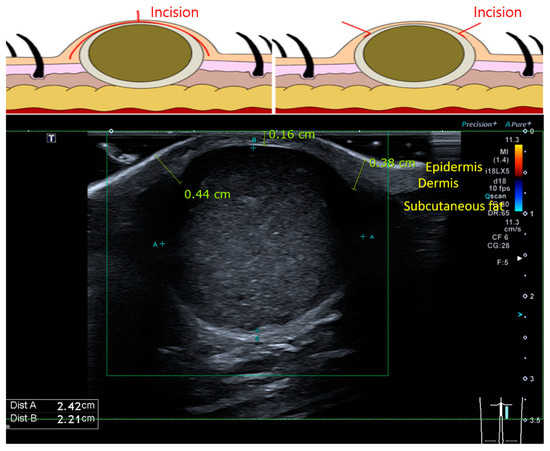

1. Introduction

2.1. Patient Selection and Surgical Methods